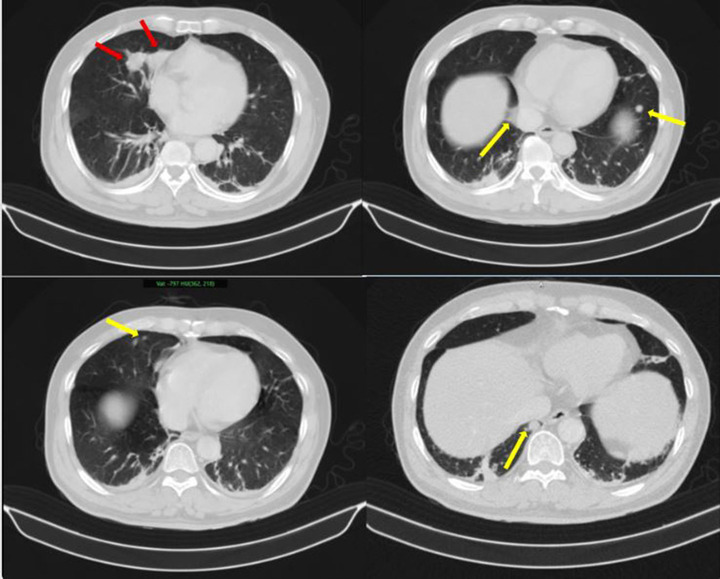

Những hình ảnh bất thường trên phổi của bệnh nhân (Ảnh: BV Bạch Mai)

Kết quả sinh thiết và phân tích mô bệnh học kết hợp hóa mô miễn dịch giúp làm rõ: khối u phổi là ung thư biểu mô tuyến của phổi, trong khi khối u tuyến tiền liệt là ung thư biểu mô tuyến với điểm Gleason 9 - thuộc nhóm nguy cơ cao. Hai loại ung thư này có nguồn gốc hoàn toàn khác nhau, không phải di căn chéo.